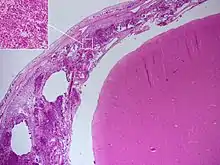

Autopsie

Le diagnostic de méningite peut être porté après la mort lorsqu'une autopsie est réalisée, montrant une inflammation de la pie mère et de l'arachnoïde avec des neutrophiles pouvant gagner le système nerveux central via les nerfs ou les vaisseaux méningés, parfois entourés de pus[36].